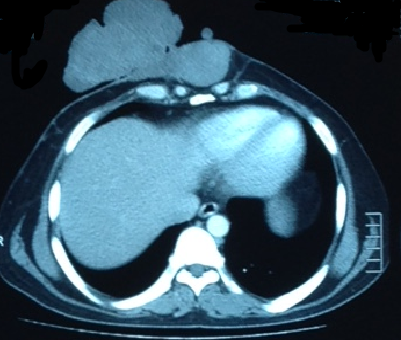

The authors performed preoperative staging examination and imaging. There was no evidence of tumor apart from what was on the chest wall. He had an incisional biopsy that demonstrated angiomyxoma. On the computed tomography (CT) scan, the tumor was above the facial plane of the chest (Figure 2).